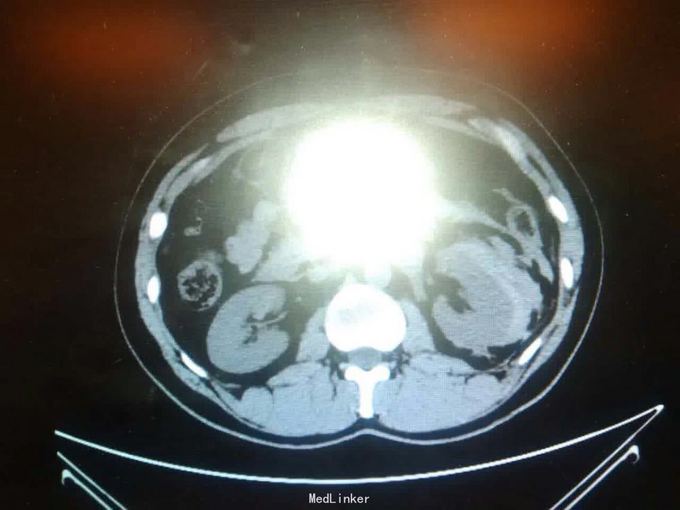

左肾下级错构瘤破裂伴出血

发现错构瘤五年余,破裂3小时

泌尿系ct

肾挫伤,及时手术治疗,行肾脏全切术